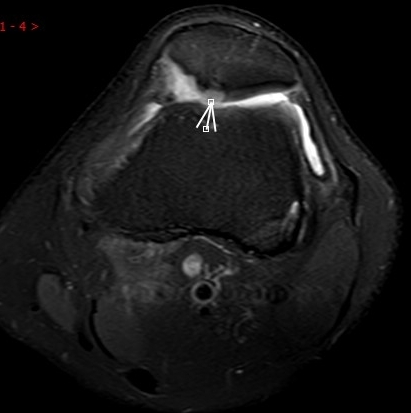

1. “咯吱响”+“卡顿感”——半月板的“碎玻璃警报”

场景:下蹲时膝盖“咯噔”弹响,起身像被“卡住”

MRI侦查:精准捕捉半月板撕裂或变性(半月板内高信号),避免拖成“关节交锁”

(半月板撕裂)